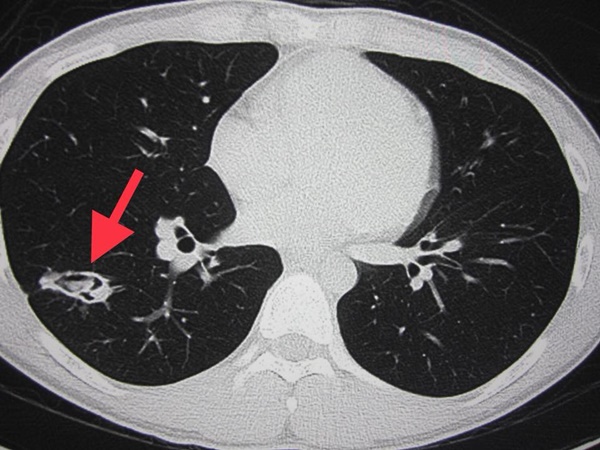

นพ.มนูญ อธิบายว่า คนไข้คนนี้มีเห็ดในปอดจากการสูดดมสปอร์ของเห็ด เนื่องจากสปอร์เห็ดมีขนาดเล็กมากจึงสามารถเข้าสู่ปอดได้ อีกทั้งคนไข้ยังหายใจเอาเชื้อราจากขี้นกพิราบเข้าไปด้วย ทำให้ติดเชื้อถึง 2 ชนิดพร้อมกัน ซึ่งเกิดขึ้นน้อยมากและยังไม่มีใครรายงานมาก่อน สำหรับการรักษาจำเป็นต้องผ่าตัด เพราะไม่มียารักษาโรคจากเห็ด โดยได้ให้ยารักษาเชื้อราจากขี้นกพิราบต่อจนครบ 1 ปี สรุปจากการติดตามผู้ป่วยมา 4 ปี ปัจจุบันหายเป็นปกติ ดังนั้นจึงไม่ควรสูดดมเห็ดสดทุกชนิด เพราะเห็ดอาจทำให้เกิดฝีในปอด พร้อมทั้งหลีกเลี่ยงอยู่ใกล้ขี้นกพิราบด้วย